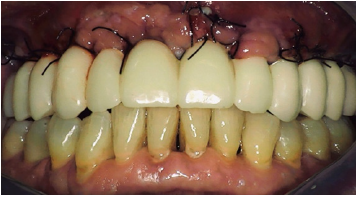

In the resulting post-surgical intermaxillary space, a fixed full-arch temporary prosthesis was digitally designed and manufactured in a complete digital workflow (CAD/CAM) with the occlusal plane parallel to the Camper’s plane and the bipupillary plane, it was then screwed on the implants (Figures 7-12). The definitive prosthesis will be fabricated once the implants are integrated and both hard and soft tissue are healed and stable.

Figure 11: Final aesthetic result.

As seen in the previous case, in the resulting post-surgical intermaxillary space, a fixed full-arch temporary prosthesis was digitally designed and manufactured in a complete digital workflow (CAD/CAM) with the occlusal plane parallel to the Camper’s plane and the bipupillary plane, it was then screwed on the implants (Figures 15-22). The definitive prosthesis will be fabricated once the implants are integrated and both hard and soft tissue are healed and stable.

Figure 18: Temporary maxillary full-arch prosthesis screwed on the implants immediately after surgery.